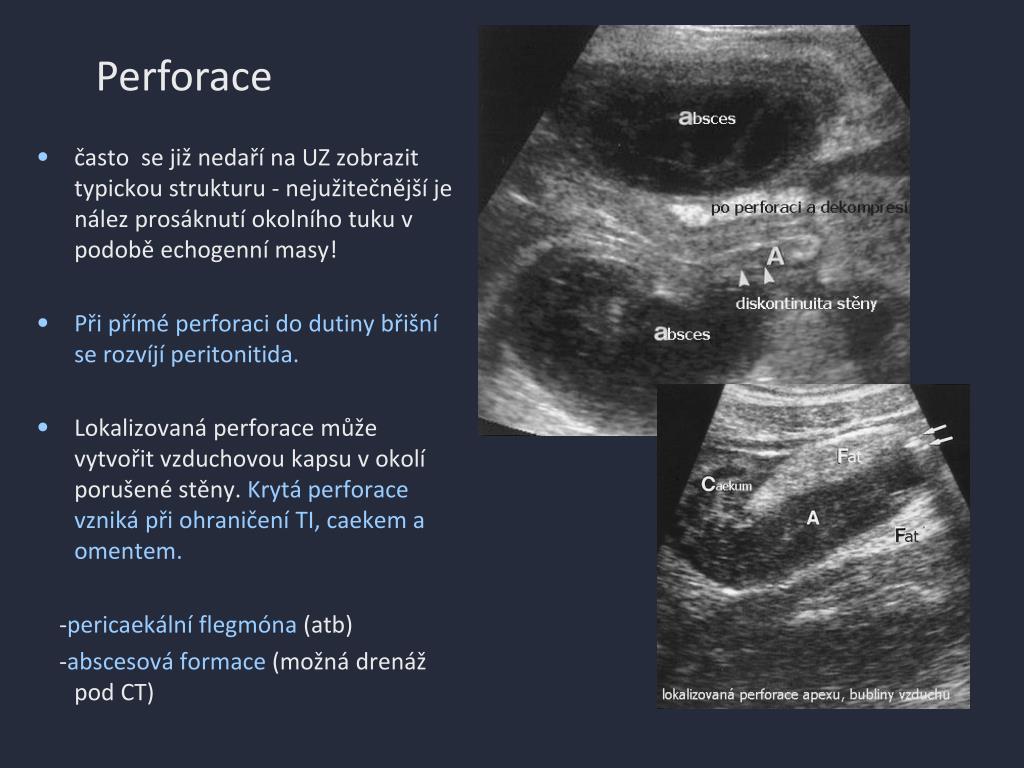

9. Perforace • často se jižnedaří na UZ zobrazit typickou strukturu - nejužitečnější je nález prosáknutí okolního tuku v podobě echogenní masy! • Při přímé perforaci do dutiny břišní se rozvíjí peritonitida. • Lokalizovaná perforace může vytvořit vzduchovou kapsu v okolí porušené stěny. Krytá perforace vzniká při ohraničení TI, caekem a omentem. -pericaekální flegmóna (atb) -abscesová formace (možná drenáž pod CT)